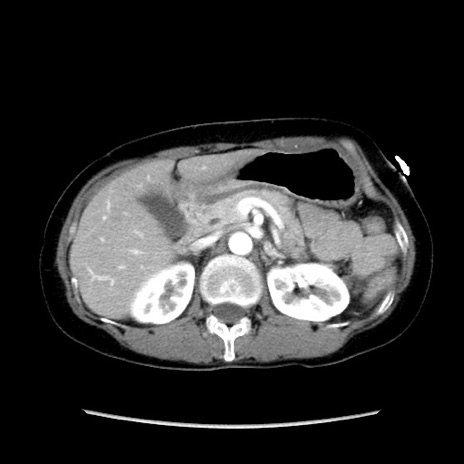

症例32(横断像)

【症例】40歳代 女性

【主訴】上腹部痛、嘔気・嘔吐

【現病歴】約9時間前頃から急に上腹部痛、嘔気、嘔吐が出現。改善しないため救急要請。

【既往歴】子宮頚癌(広汎子宮全摘術、放射線療法)、腸閉塞